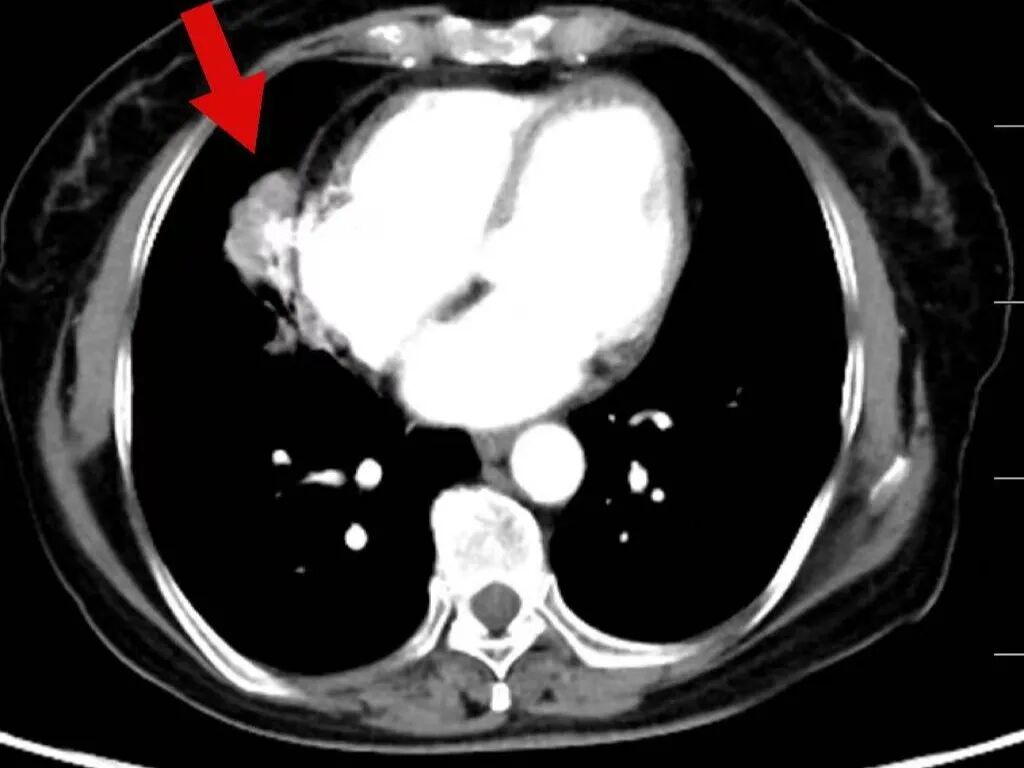

2025年3月17日,肿瘤诊疗中心团队首次为毕女士成功实施BACE治疗。术后患者病情暂时稳定,但5月10日复查显示肺部原发病灶稳定,肝脏转移病灶再次增大。

面对病情反复,团队没有放弃,果断升级治疗方案,决定同期施行BACE联合肝动脉化疗栓塞术,继续强化局部控制。“对于这类晚期患者,局部介入的优势在于能够高效、低毒地控制关键病灶。”介入医学科主任杨亚平说,“BACE联合肝动脉栓塞这类技术既能提高肿瘤部位的药物浓度,又减少了全身副作用,为后续治疗创造了条件。”

在玉溪市中山医院肿瘤诊疗中心治疗后,肿瘤在明显缩小